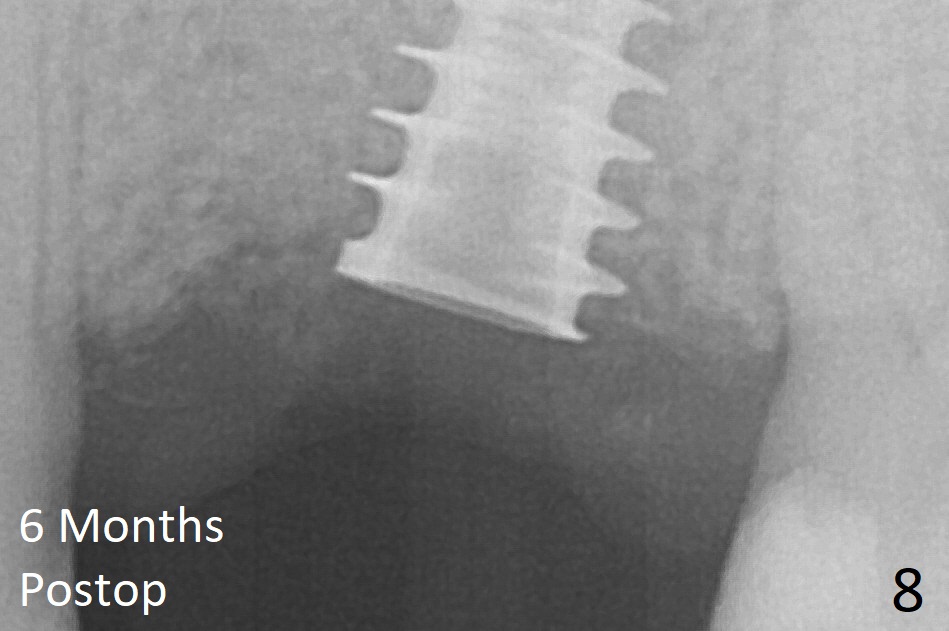

The implant is mobile 4 months postop (Fig.6).  A 6x2 mm healing abutment is placed next.  Although the implant remains mobile 6 months postop, the bone seems to have become denser around the implant (Fig.7-9).  A healing screw is placed.  When the bone height is limited (<7 mm), place a larger implant (>5.5 mm).  The implant seems to have osteointegrated 8 months postop (Fig.10).  Impression is taken following placing a 6.5x4(3) mm abutment.  The patient reports pain after cementation, which is less when the abutment screw is loose (9.5 months postop, 2 weeks post cementation).  CBCT taken after placement of a healing screw apparently shows loose bone mesial and distal to the implant (Fig.11 *).  The implant trajectory is less favorable.  It seems necessary to change to a large implant with more sold threads (Fig.12).